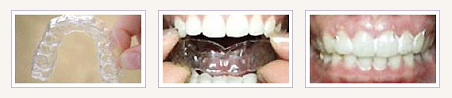

투명필름교정장치는 금속으로 된 와이어나 브라켓을 사용하지 않고 투명하게 만들어져 치열을 교정할 수 있는 장치입니다

교정치료가 완료된후 치아는 원래의 자리로 돌아가려는 성질이 있습니다. 이를 막기위해 치료된 상태를 유지하기 위한 장치를 보정장치(retainer)라고 합니다. 보정장치에는 고정식 장치와 가철식 장치가 있습니다.

투명교정치료는 철사나 브라켓같은 장치를 사용하지 않고 투명한 플라스틱 교정장치를 통해 교정치료를 하는 방법입니다. 환자의 교정상태에 따라 계속 바꾸어 착용하게 되는데 순차적으로 교정장치를 착용하면 비뚤어진 치아가 조금씩 움직여 나중에는 가지런한 치열을 가지게 됩니다. 투명교정치료는 악골의 이상이 없는 경우 그리고 어금니부위의 교합상태가 좋은 경우에 앞이 부분만 비뚤어졌거나, 공간이 생긴 경우에 가능한 치료법입니다. 또한 교정치료후 재발이 된 경우 재발을 치료하기 위한 방법으로도 사용할 수 있습니다. 따라서 투명교정치료는 다른 교정장치를 사용하지 않고도 가능한지의 여부를 반드시 상담 받으셔야 합니다.